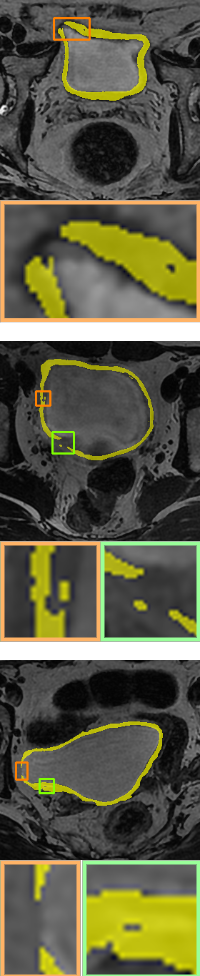

We compare the results of no topological constraints (without-topo), topological constraints without width (PH), and width-aware topological constraints (WT) applied to a number of data-driven models for relevant applications. As can be seen in Table 3, our proposed method (rows with gray background) shows superior performance. Specifically, the improvements in volumetric demonstrate that our method has more accurate result in a pixel-level sense, while the improvements on topology-based metrics demonstrate that WT energy has an overall more precise prediction and topological similarity. For boundary-based indicators, WT performs better compared to PH in most cases due to the width information. The corresponding visualization is given in Fig. 10 and Fig. 11. From the visualization results, it can be seen that in data-driven image segmentation models, no topological constraints will produce obvious topological errors, even if its segmentation results have high accuracy. When constraining topological consistency using persistent homology methods, it may be possible to connect very thin lines to ensure connectivity or a consistent number of holes. We improve the PH method by smoothing the critical points in there structuring elements neighborhood, which can preserve the width information while constraining the topological properties to be consistent.

Ground-truth

Without-topo

PH[ph]

Proposed WT